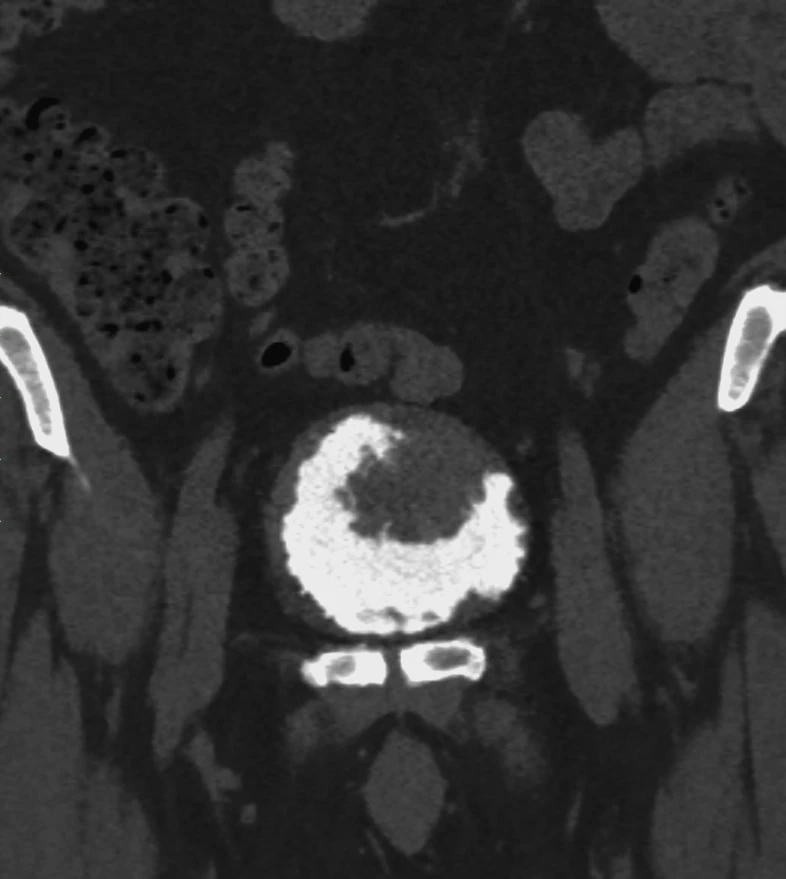

Классные тератомы. 30 лет.

В ОРАЦ есть интересный момент: когда речь о тератоме, то надо оценить, есть ли значительное количество ткани, накапливающей контраст. Субъективная вещь. Один сочтёт, что значительное, другой сочтёт, что не значительное. Но в первом случае это будет четвёртая категория и опухоли надо удалять, а во втором случае это будет вторая категория, и можно просто спокойно понаблюдать. Только что переубедил коллегу написать двойку вместо четвёрки по этим картинкам.

Кривую показываю на всякий случай, она на присвоение категории в данном случае не влияет, но дополнительно успокаивает, что ли. А зубчатость её объясняется тем, что исходные изображения и изображения после субтракции представляют собой одну серию, а вручную их разделять мне было лень. На информативность кривой это никак не влияет.

Видно, что в миометрии контраст накапливается гораздо быстрее и гораздо сильнее. То есть, если бы это на что-то влияло, то эту кривую надо было бы расценить, как кривую низкого риска.